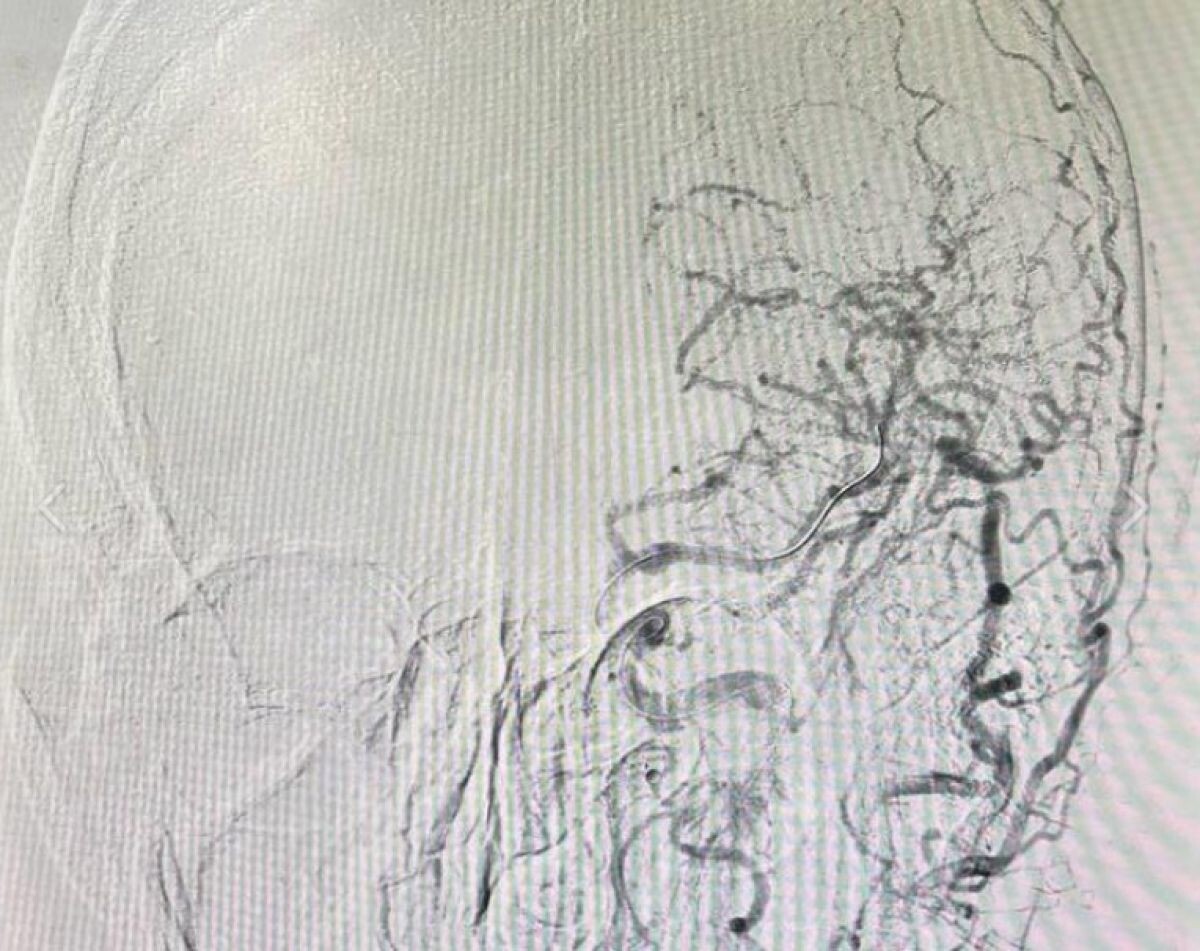

Медики Орловской областной клинической больницы успешно провели сложнейшую операцию при инсульте. Об этом сообщили на странице медучреждения. В больницу был экстренно доставлен 70-летний пациент с острым ишемическим инсультом. У мужчины наблюдались серьезные нарушения - паралич правой стороны тела и потеря речи. Обследование показало закупорку средней мозговой артерии. Нейрохирурги выполнили экстренную эндоваскулярную операцию - через прокол в бедре они удалили тромб, восстановив кровоснабжение мозга. Уже во время процедуры у пациента появились движения в парализованных конечностях, а через три часа начала восстанавливаться речь. После курса реабилитации больной был выписан без неврологических нарушений.